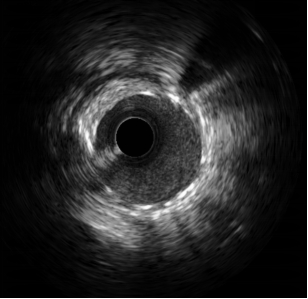

术中,造影结果与术前判断一致,患者前降支血管重度狭窄且病变累及较大分支血管开口,需要介入治疗。公永太教授带领介入团队,凭借精湛的手术技巧,首先分别于前降支及分支送入导丝,在分支预埋球囊保护下,于前降支病变部位置入一枚支架,之后再送入导丝穿支架网眼至分支内,完成球囊后扩张和对吻扩张。操作过程中采用IVUS评估病变、优化支架置入,全程未使用对比剂。整个手术的对比剂用量不足15ml,远远少于一例普通患者单纯造影所用剂量。患者术后复查肌酐无增高,心绞痛症状完全缓解,顺利出院。

IVUS示支架贴壁、膨胀良好

李悦副院长介绍,冠脉介入治疗全程需要造影剂显影指导下完成,而造影剂是通过肾脏代谢,对于肾功能正常人群来说,仅需要术前术后适当增加饮水即可。但对于肾功能不全患者如使用大量造影剂,可能加重肾功能损害,严重者可导致急性肾衰竭,需要透析治疗。对于此类患者,经验丰富的术者可借助腔内影像学手段指导介入操作,精确选择支架直径、长度及着陆点并指导支架优化置入,可极大减少甚至完全无需使用对比剂,有效保护患者残余肾脏功能。